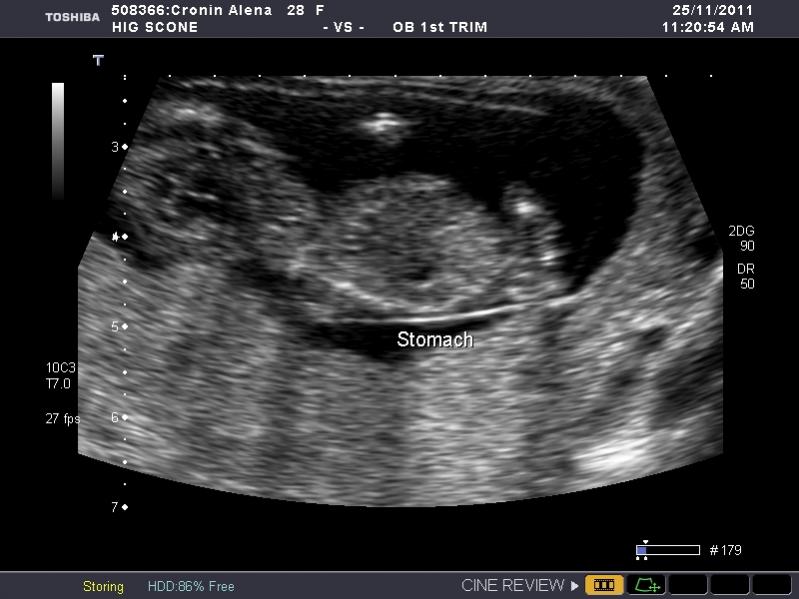

I have heaps of photos and I don't know what I am looking at so if the photo I post isn't showing anything let me know and I will try another. I am nervous as anything because I so so want a girl, but of course would still be happy with a boy. The ultrasound tech wouldn't guess.

So what is your guess.